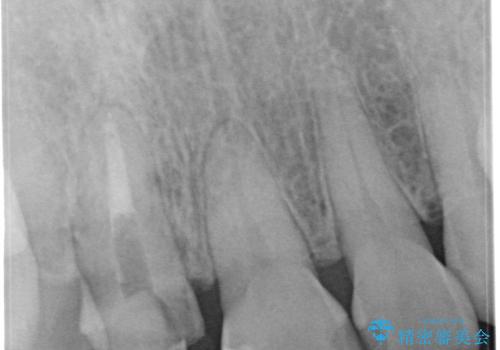

10年前に根管治療を他院で行っており、根尖性歯周炎の予防のため根管治療から行いました。被せものはオールセラミッククラウンで治療を行いました。

- 30.8万円(税込) 内訳:根管治療 12.1万円 ファイバーコア 2.2万円 仮歯 1.1万円 オールセラミッククラウン(スペシャル) 14.3万円 ホームホワイトニング 1.1万円 費用は治療当時の料金となります

10年前にラバーダムシート無しに根管治療を行っており、現在、症状は出ていませんが、根尖性歯周炎の予防のため根管治療から行いました。ホームホワイトニングを2週間行って頂き、その後、オールセラミッククラウンで治療を行っています。

※ファイバーコアとは、根管治療後、歯に立てる土台の事です。金属の土台と比べ歯根破折のリスクが低く、白いのが特徴です。